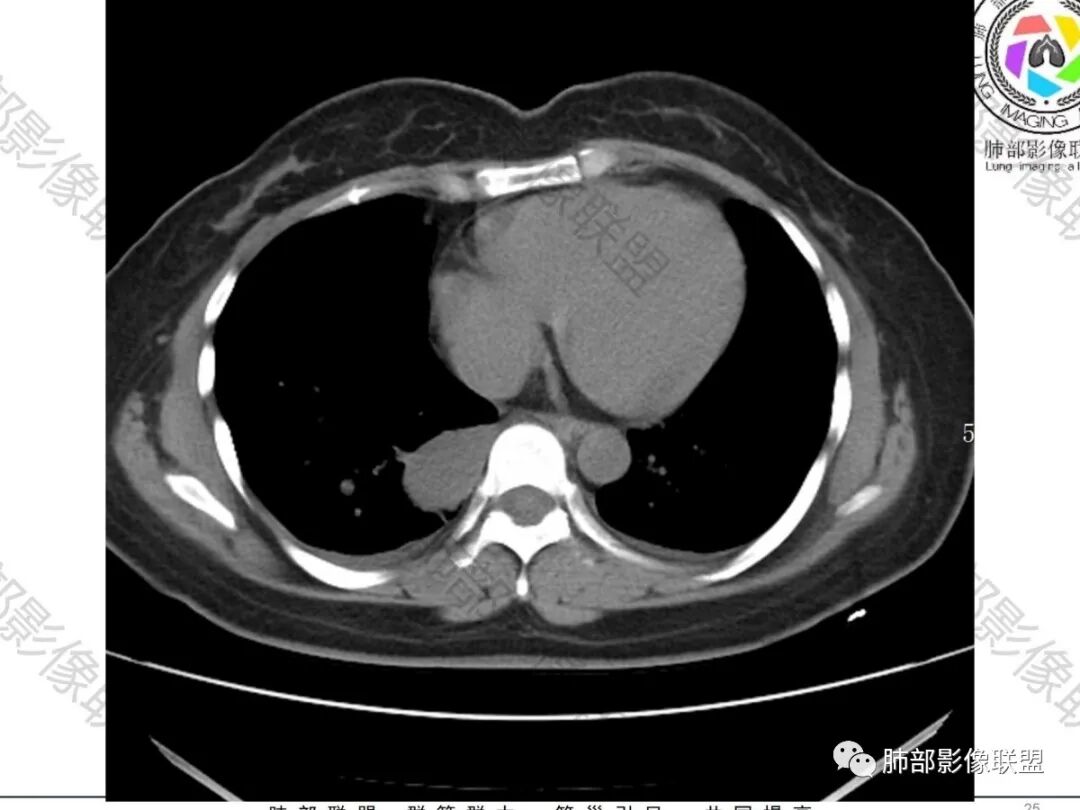

2.右肺下叶脊柱旁类椭圆形块影,边界清楚,密度偏低,隐约见轻度强化囊壁样结构,均匀一致,中央区域未见强化,因属囊样块影。前外缘处显示“壁外”小范围轻度强化软组织密度影,未见磨玻璃晕。

3.块影边缘见匍行血管影,未显示体循环供血。病灶与支气管关系未能显示或呈现。

病灶相邻胸膜轻度强化,未见壁层胸膜侵入或突破。

4.双肺门及纵隔未见增大淋巴结。

5.右侧胸腔少量积液。